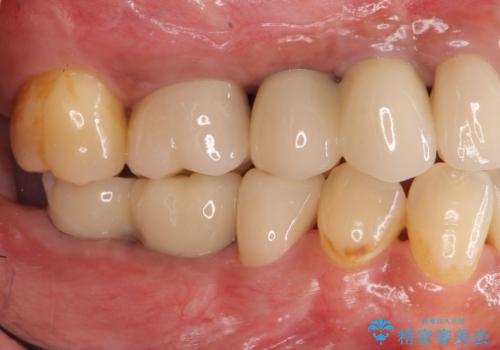

安定する噛み合わせの位置を探りながらの治療となりました。

最終的に非常に安定した咬合関係を構築できたので、しっかりとどんな食事でも楽しめると同時に、清掃性も高く清潔な口腔内環境を確立できました。